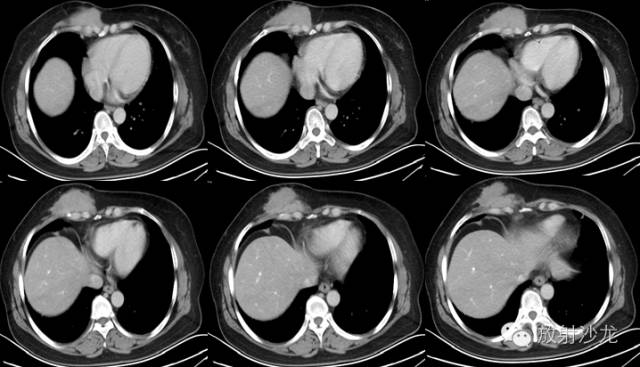

2. 主 诉:发现右侧前胸壁肿物伴间断疼痛3年,进行性增大1年

3.现病史:约3年前发现右侧前胸壁肿物,初始发现时约1cm×1cm大小,伴钝性疼痛,呈间断性,休息后缓解,不伴胸憋、气紧、咳嗽、发热、盗汗等症状,不伴牵扯性疼痛,未予重视。1年前右侧前胸壁肿物进行性增大,仍伴间断性疼痛

4. 专科检查:胸廓无畸形,双乳对称,无红肿,无触痛。右侧前胸壁可触及一大小约13cm×6cm的不规则形皮下肿物,越过胸骨正中线,表面不平,其上可见两处范围分别为4cm×3cm、2cm×1cm的皮肤发红区域,触之质韧,边界不清,活动度差,无皮温增高及波动感,无明显压痛

CT表现:CT对侵袭性纤维瘤病的诊断无特异性,CT常表现为肿瘤沿肌肉长轴生长,边缘规则或不规则,密度基本均匀,增强扫描可见强化。CT扫描能提示病变的性质并能正确评价病变侵犯的范围,对制订恰当的治疗方案及减少复发机会有明显价值口。